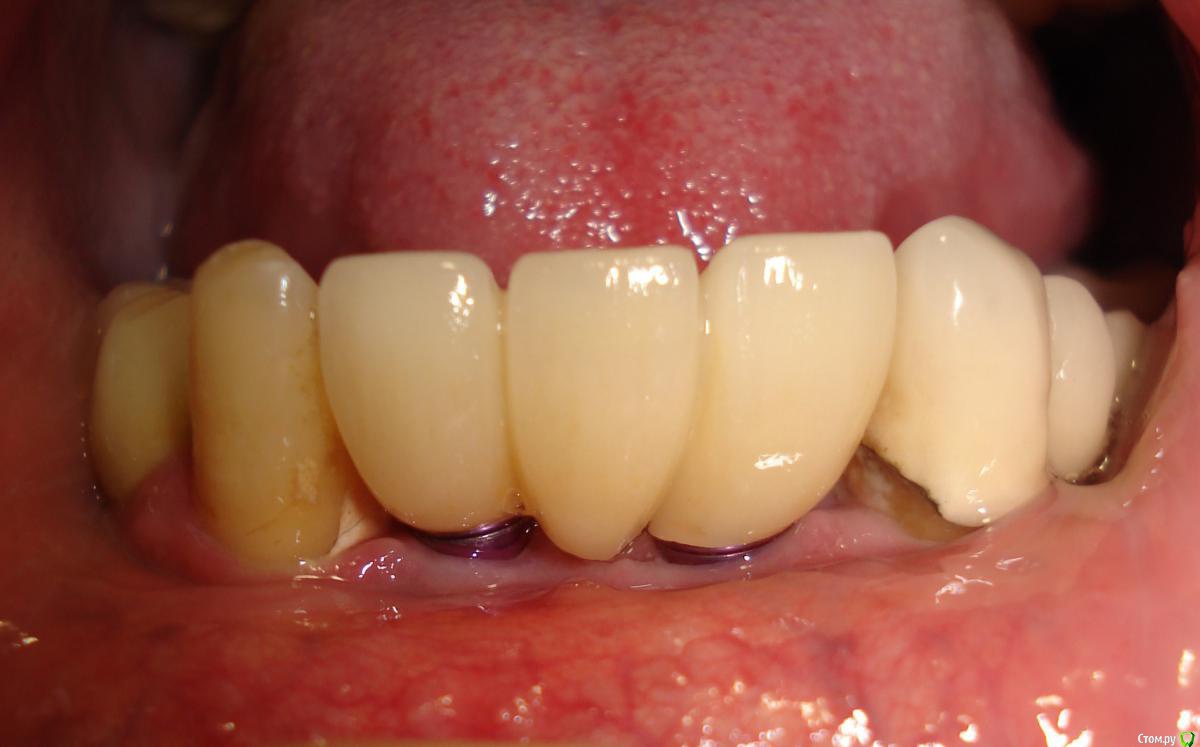

Antikwar Опубликовано 26 ноября, 2017 Поделиться Опубликовано 26 ноября, 2017 Доброго времени суток .Хотелось бы узнать компетентное мнение, врачей, З.техников. Вчера было установленно 2 моста (оксид циркония) на имплантанты перед низ и 2 коронки с боку правая сторона низ ..НА мой не опытный взгляд конструкция и сама работа не качественная и эстетика здесь полностью отсутствует. 1.Видно тело абатмента в обоих конструкциях. 2.Мост и коронки висят в воздухе и не прилегают к десне,как в первом так и во втором случае. Между десной и мостом (перед низ) проходит спичка. Вопрос, должен ли мой доктор переделать эту (на мой взгляд) не качественную работу ! Что вы мне посоветуете .... Заранее благодарю всех откликнувшихся. Ссылка на комментарий

chervoncevdaniil Опубликовано 26 ноября, 2017 Поделиться Опубликовано 26 ноября, 2017 Доброго времени суток .Хотелось бы узнать компетентное мнение, врачей, З.техников. Вчера было установленно 2 моста (оксид циркония) на имплантанты перед низ и 2 коронки с боку правая сторона низ ..НА мой не опытный взгляд конструкция и сама работа не качественная и эстетика здесь полностью отсутствует. 1.Видно тело абатмента в обоих конструкциях. 2.Мост и коронки висят в воздухе и не прилегают к десне,как в первом так и во втором случае. Между десной и мостом (перед низ) проходит спичка. Вопрос, должен ли мой доктор переделать эту (на мой взгляд) не качественную работу ! Что вы мне посоветуете .... Заранее благодарю всех откликнувшихся.СУдя по фото у вас убыль костной и мягких тканей в области ипмлантов.А состояние соседних коронок на зубах вас не смущают? Ссылка на комментарий

Pavel-Pskov Опубликовано 27 ноября, 2017 Поделиться Опубликовано 27 ноября, 2017 Скорее всего для приемлемого эстетического результата нужна мягкотканная аугментация. А по поводу," куда вы смотрели", посещение стоматолога для многих стресс, и все нюансы пациент не всегда в состоянии сразу оценить. 5 Ссылка на комментарий

red_butler Опубликовано 27 ноября, 2017 Поделиться Опубликовано 27 ноября, 2017 Вопрос, должен ли мой доктор переделать эту (на мой взгляд) не качественную работу ! этот вопрос должен лежать в правовой плоскости страны в которой проводилось лечение.Улучить результат можно мягкотканной пластикой, возможно несколькими. Временным протезированием и новой конструкцией. Ссылка на комментарий

krokomot Опубликовано 27 ноября, 2017 Поделиться Опубликовано 27 ноября, 2017 целевая зона на снимке замылена, четкости нет, исходя из ваших фотографий проблемма не в коронках, а в позиции имплантатов - видна шейка имплантата, так быть не должно. нужны прицельные снимки этой области. Учитывая обстоятельства коронки изготовливаются исходя из положения имплантатов.и я так понимаю вас запротезировали из позиции то что есть, и вая явно нужно что-то делать. Ссылка на комментарий